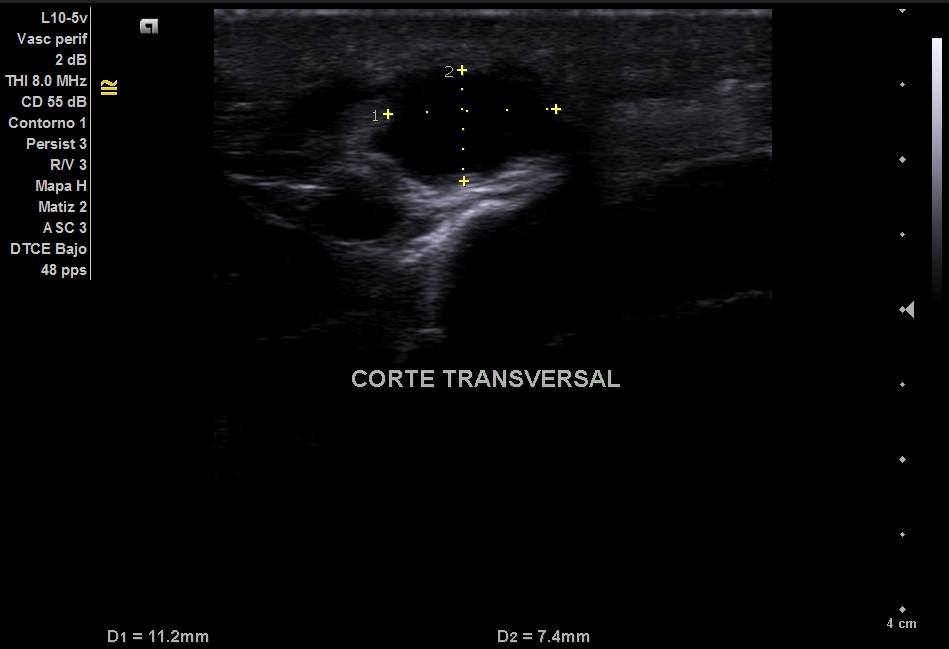

Imagen 2: Corte transversal del aneurisma

Imagen hipoecoica de 11,2 x 7,4 mm.